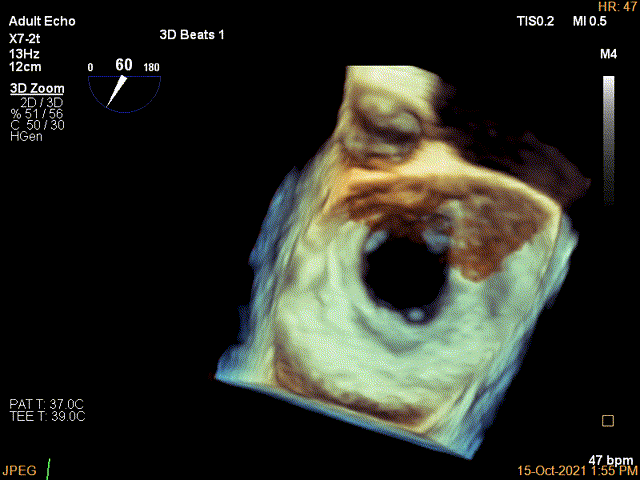

3D-color MV view:极大量返流,1、2区均有受累

Qlab软件勾画估测瓣口面积约:6.23cm²